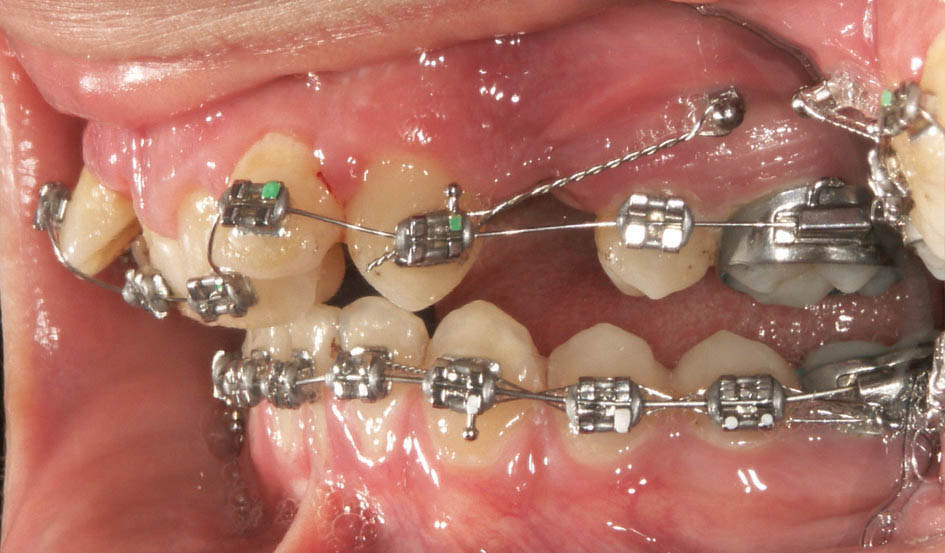

اگر قرار است خلفیها اصلاً جلو نیایند باید مینی اسکرو بگذارید (شکل 24-3) بدین صورت فضای بدست آمده از کشیدن پرمولر خرج دیستاله شدن قدامیها میشود. اگر بیمار در فک بالا دچار کرادینگ شدید باشد و اورجت زیادی نداشته باشد، مصرف فضای پرمولر اثری روی نیمرخ صورت ندارد، اما اگر در فک بالا کرادینگ نداشته باشد و اورجت زیاد باشد آن موقع با عقب رفتن قدامیها شاهد تو افتادن لب بالا خواهیم بود (شکل 25-3 و 26-3)

شکل 24-3: بیمار با اکلوژن یک کاسپ کامل کلاسII و پروتروژن. اعمال تمام نیروها به مینی اسکرو بعد از کشیدن پرمولر اول.